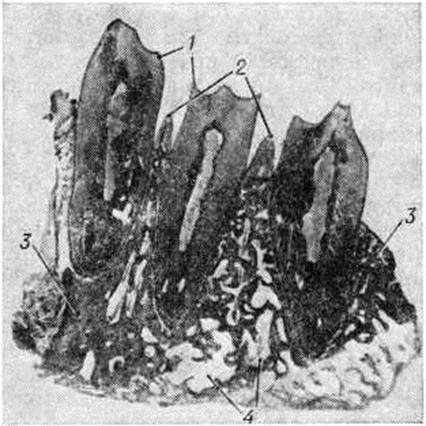

Патологическая анатомия. Пародонтоз начинается обычно с воспаления десны, протекающего как хронический катаральный гингивит (смотри полный свод знаний). В просвете десневой борозды образуются обильные напластования рыхлых базофильных масс, включающие колонии микробов и единичные эпителиальные клетки. Позже на основе богатого микробной флорой над и поддесневого плотного налёта формируется зубной камень (смотри полный свод знаний), который усугубляет патологический изменения пародонта. Хронический гингивит сопровождается воспалительной инфильтрацией десны лимфоидными, плазматическими клетками, отёком десны, активной пролиферацией, вегетацией в подлежащую соединительнотканную основу десны, а также усилением слущивания эпителиальных клеток. Состав клеточного инфильтрата (лимфоидные и плазматические клетки) характерен для реакции гиперчувствительности замедленного типа. Уже на этой стадии заболевания в костной ткани пародонта обнаруживается нерезко выраженная лакунарная резорбция кости альвеолярного отростка (цветной таблица, ст. 369, рисунок 1, 2).

Следующим этапом патологический процесса является формирование пародонтального кармана, характеризующееся разрушением эпителиального покрова в области зубодесневого соединения, вегетацией пластов эпителия в глубь периодонтальной щели. При электронной микроскопии, по данным Карсона и Сейга (R. Е. Carson, Е. S. Sayegh, 1978), отмечается исчезновение коллагеновых фибрилл периодонтальной связки, в норме вплетающихся в цемент. Содержимым пародентального кармана является некротический детрит — бесструктурные, базофильные и оксифильные массы с колониями микробов и разрушенными лейкоцитами. Наружные стенки и дно пародонтального кармана образованы грануляционной тканью, пронизанной ветвящимися пластами многослойного плоского эпителия. В костных структурах альвеолярного отростка наблюдаются выраженные резорбтивные изменения (цветной рисунок 3), начинающиеся в области верхушки альвеолярного отростка и приводящие к её полному рассасыванию. В последующем резорбтивные лакуны, содержащие остеокласты, появляются в нижележащих отделах стенок зубных альвеол, что ведёт к постепенному истончению межальвеолярных костных перегородок. Одновременно отмечается разрежение губчатой кости и в толще межальвеолярных перегородок. Процесс резорбции может протекать по типу гладкого рассасывания, лакунарной резорбции, а также как онкоз (в результате приобретения костными клетками способности к остеоклазии).

На фоне патологический изменений в пародонте и по мере углубления пародонтальных карманов в прилежащих к ним участках периодонта наблюдается прогрессирование хронический воспалительного процесса. Его морфологический проявлениями являются образование густых лимфомакрофагальных инфильтратов с примесью плазматических клеток, формирование полей грануляционной ткани, а при обострении патологический процесса — солитарных, и в некоторых случаях — множественных абсцессов. При прогрессировании Пародонтоз пародонтальные карманы и реактивный по своей природе погружной рост пластов многослойного плоского эпителия достигают верхушек корней зубов, периодонтальная связка полностью разрушается. Дальнейшая резорбция костной ткани альвеолярного отростка приводит к полному рассасыванию межальвеолярных и межкорневых костных перегородок (цветной рисунок 3). При Пародонтоз в патологический процесс довольно рано вовлекаются ткани зуба: начинается резорбция цемента, что приводит к образованию глубоких цементных и цементно-дентинных ниш. Параллельно может наблюдаться процесс новообразования цемента. В случае преобладания этого процесса развивается гиперцементоз. В пульпе зубов при Пародонтоз обнаруживают выраженные в различной степени дистрофические изменения, приводящие к сетчатой её атрофии, а также к образованию в пульпе единичных и множественных петрификатов и дентиклей. Нередко при Пародонтоз отмечается развитие ретроградного пульпита, который может закончиться гибелью пульпы.